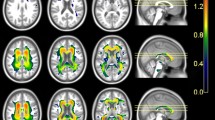

Standardized group mean ND and IF values for each region and fiber of interest, adjusted for age, sex, and education, are plotted in Fig. 1. Significant main effects of group were observed for ND in the fornix (F(2,50) = 9.23, p < 0.001), uncinate (F(2,50) = 11.03, p < 0.001), ILF (F(2,50) = 9.05, p < 0.001), IFOF (F(2,50) = 13.41, p < 0.001), and arcuate (F(2,50) = 13.13, p < 0.001), and for IF in the entorhinal cortex (F(2,50) = 21.38, p < 0.001) and hippocampus (F(2,50) = 7.35, p = 0.002). ND values were lower for MCI than HC in the uncinate and arcuate, and lower for AD than HC in the fornix, uncinate, ILF, IFOF, and arcuate (all p < 0.01). IF in the hippocampus was higher for AD than HC, and IF in the entorhinal cortex was higher for MCI and AD than HC (all p < 0.01). No significant differences between MCI and AD were observed for any measure. ND in the parahippocampal cingulum did not differ between groups (p = 0.01).

Group effects of RSI and DTI metrics. Standardized mean (± standard error) ND and IF (black bars) and FA and MD (gray bars) values, adjusted for age, sex, and education, are plotted for HC, MCI, and AD. *p < 0.01, compared to HC with Bonferroni correction for multiple comparisons. AD Alzheimer’s disease, FA fractional anisotropy, HC healthy controls, IF isotropic free water diffusion, IFOF inferior fronto-occipital fasciculus, ILF inferior longitudinal fasciculus, MCI mild cognitive impairment, MD mean diffusivity

For comparison, group effects for FA and MD within the same fibers and regions of interest as ND and IF are presented in Fig. 1. Although RSI and DTI effects were similar, there was a trend for stronger group effects for all ND measures than FA measures, and for entorhinal cortex IF than MD. Additional file 1 (Table S1) presents group effect sizes for RSI and DTI metrics.